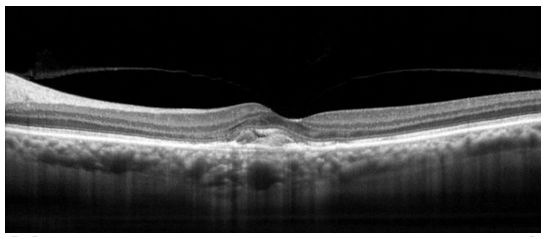

- obrazowanie przekrojów siatkówki

- moduł obrazowania i analizy plamki